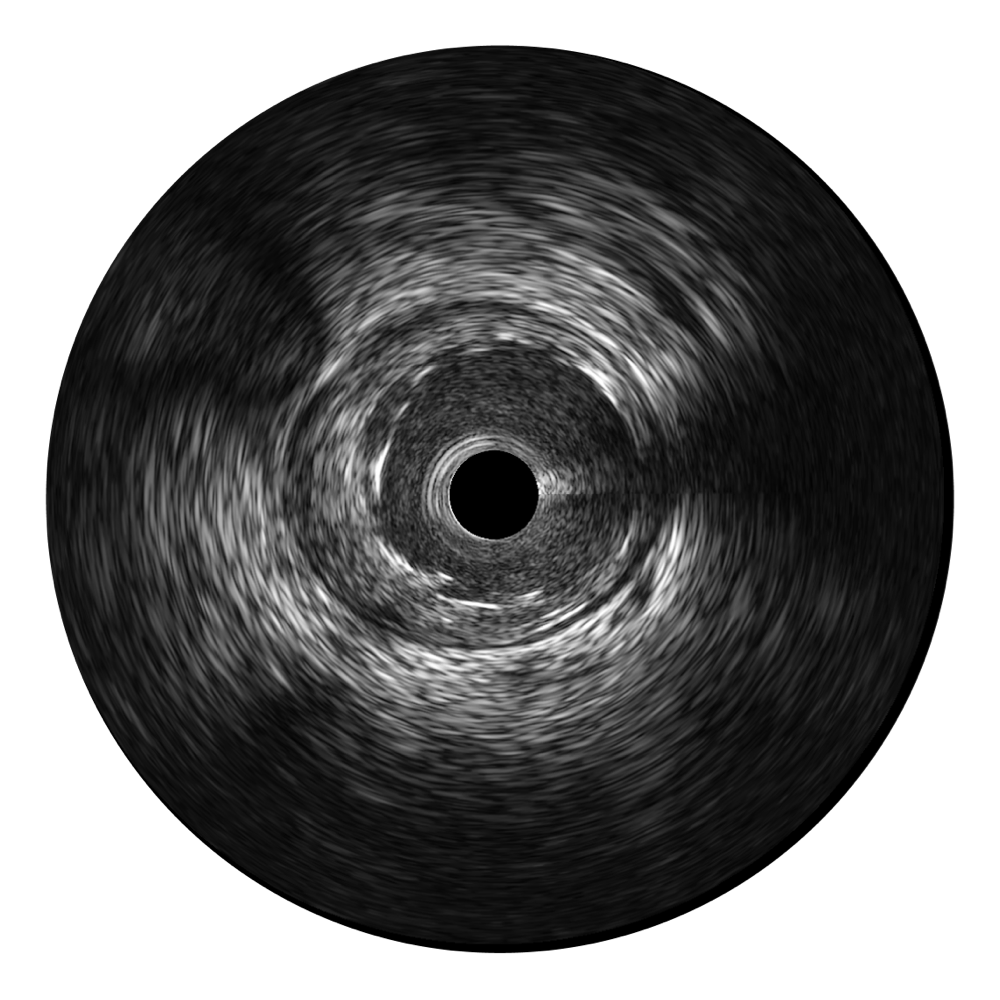

• 1xBET宽频IVUS图像

对比传统IVUS导管成像,1xBET宽频IVUS图像的近场支架梁显影更细腻,远场中膜外血管仍清晰可辨,兼顾远中近,兼顾分辨力与穿透深度